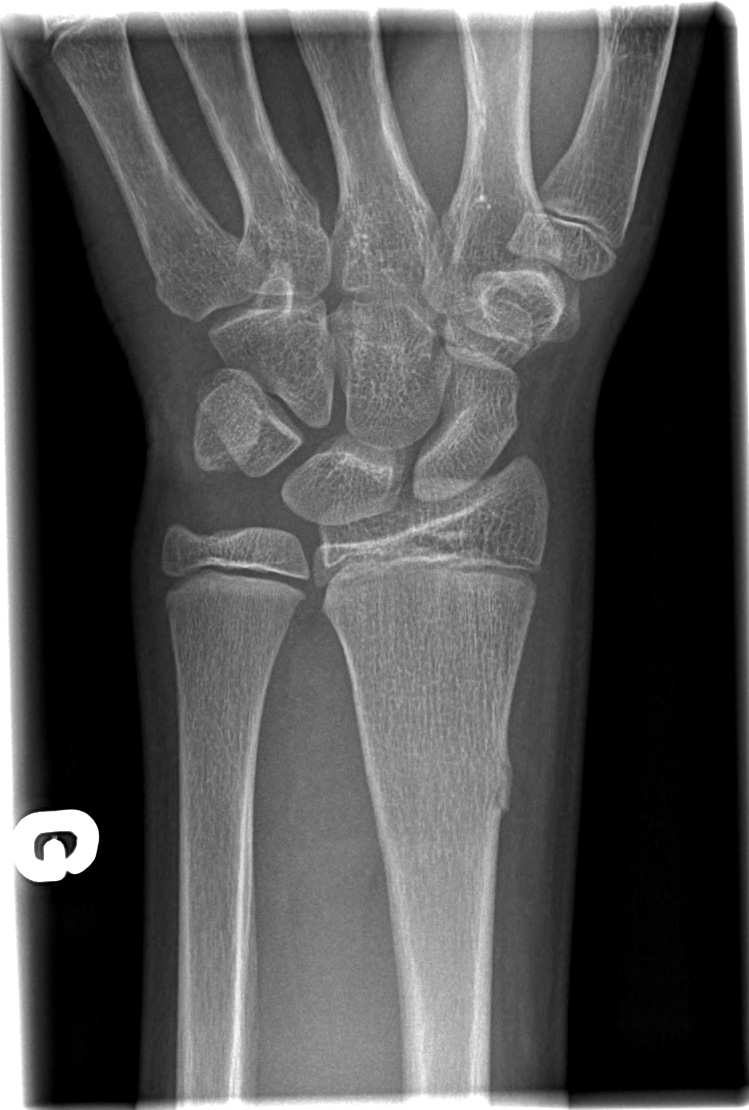

12-year-old male:

Left wrist pain after falling on a hyperextended arm and a flexed wrist.

Metaphyso-diaphyseal transverse fracture of the distal radius involving mostly the volar cortex.

Anteroposterior